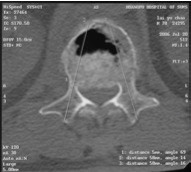

辅助检查:MRI检查示腰1椎体骨质疏松性压缩性骨折。

治疗:因患者椎体压缩骨折明显,椎体后缘骨折不完整,突入椎管,且硬膜囊受压,因此不适合行椎体成形术。给予单节段椎弓根钉固定并椎板切除减压术。骨折椎置钉结合钉道骨水泥加强稳定性。术后随访效果满意。